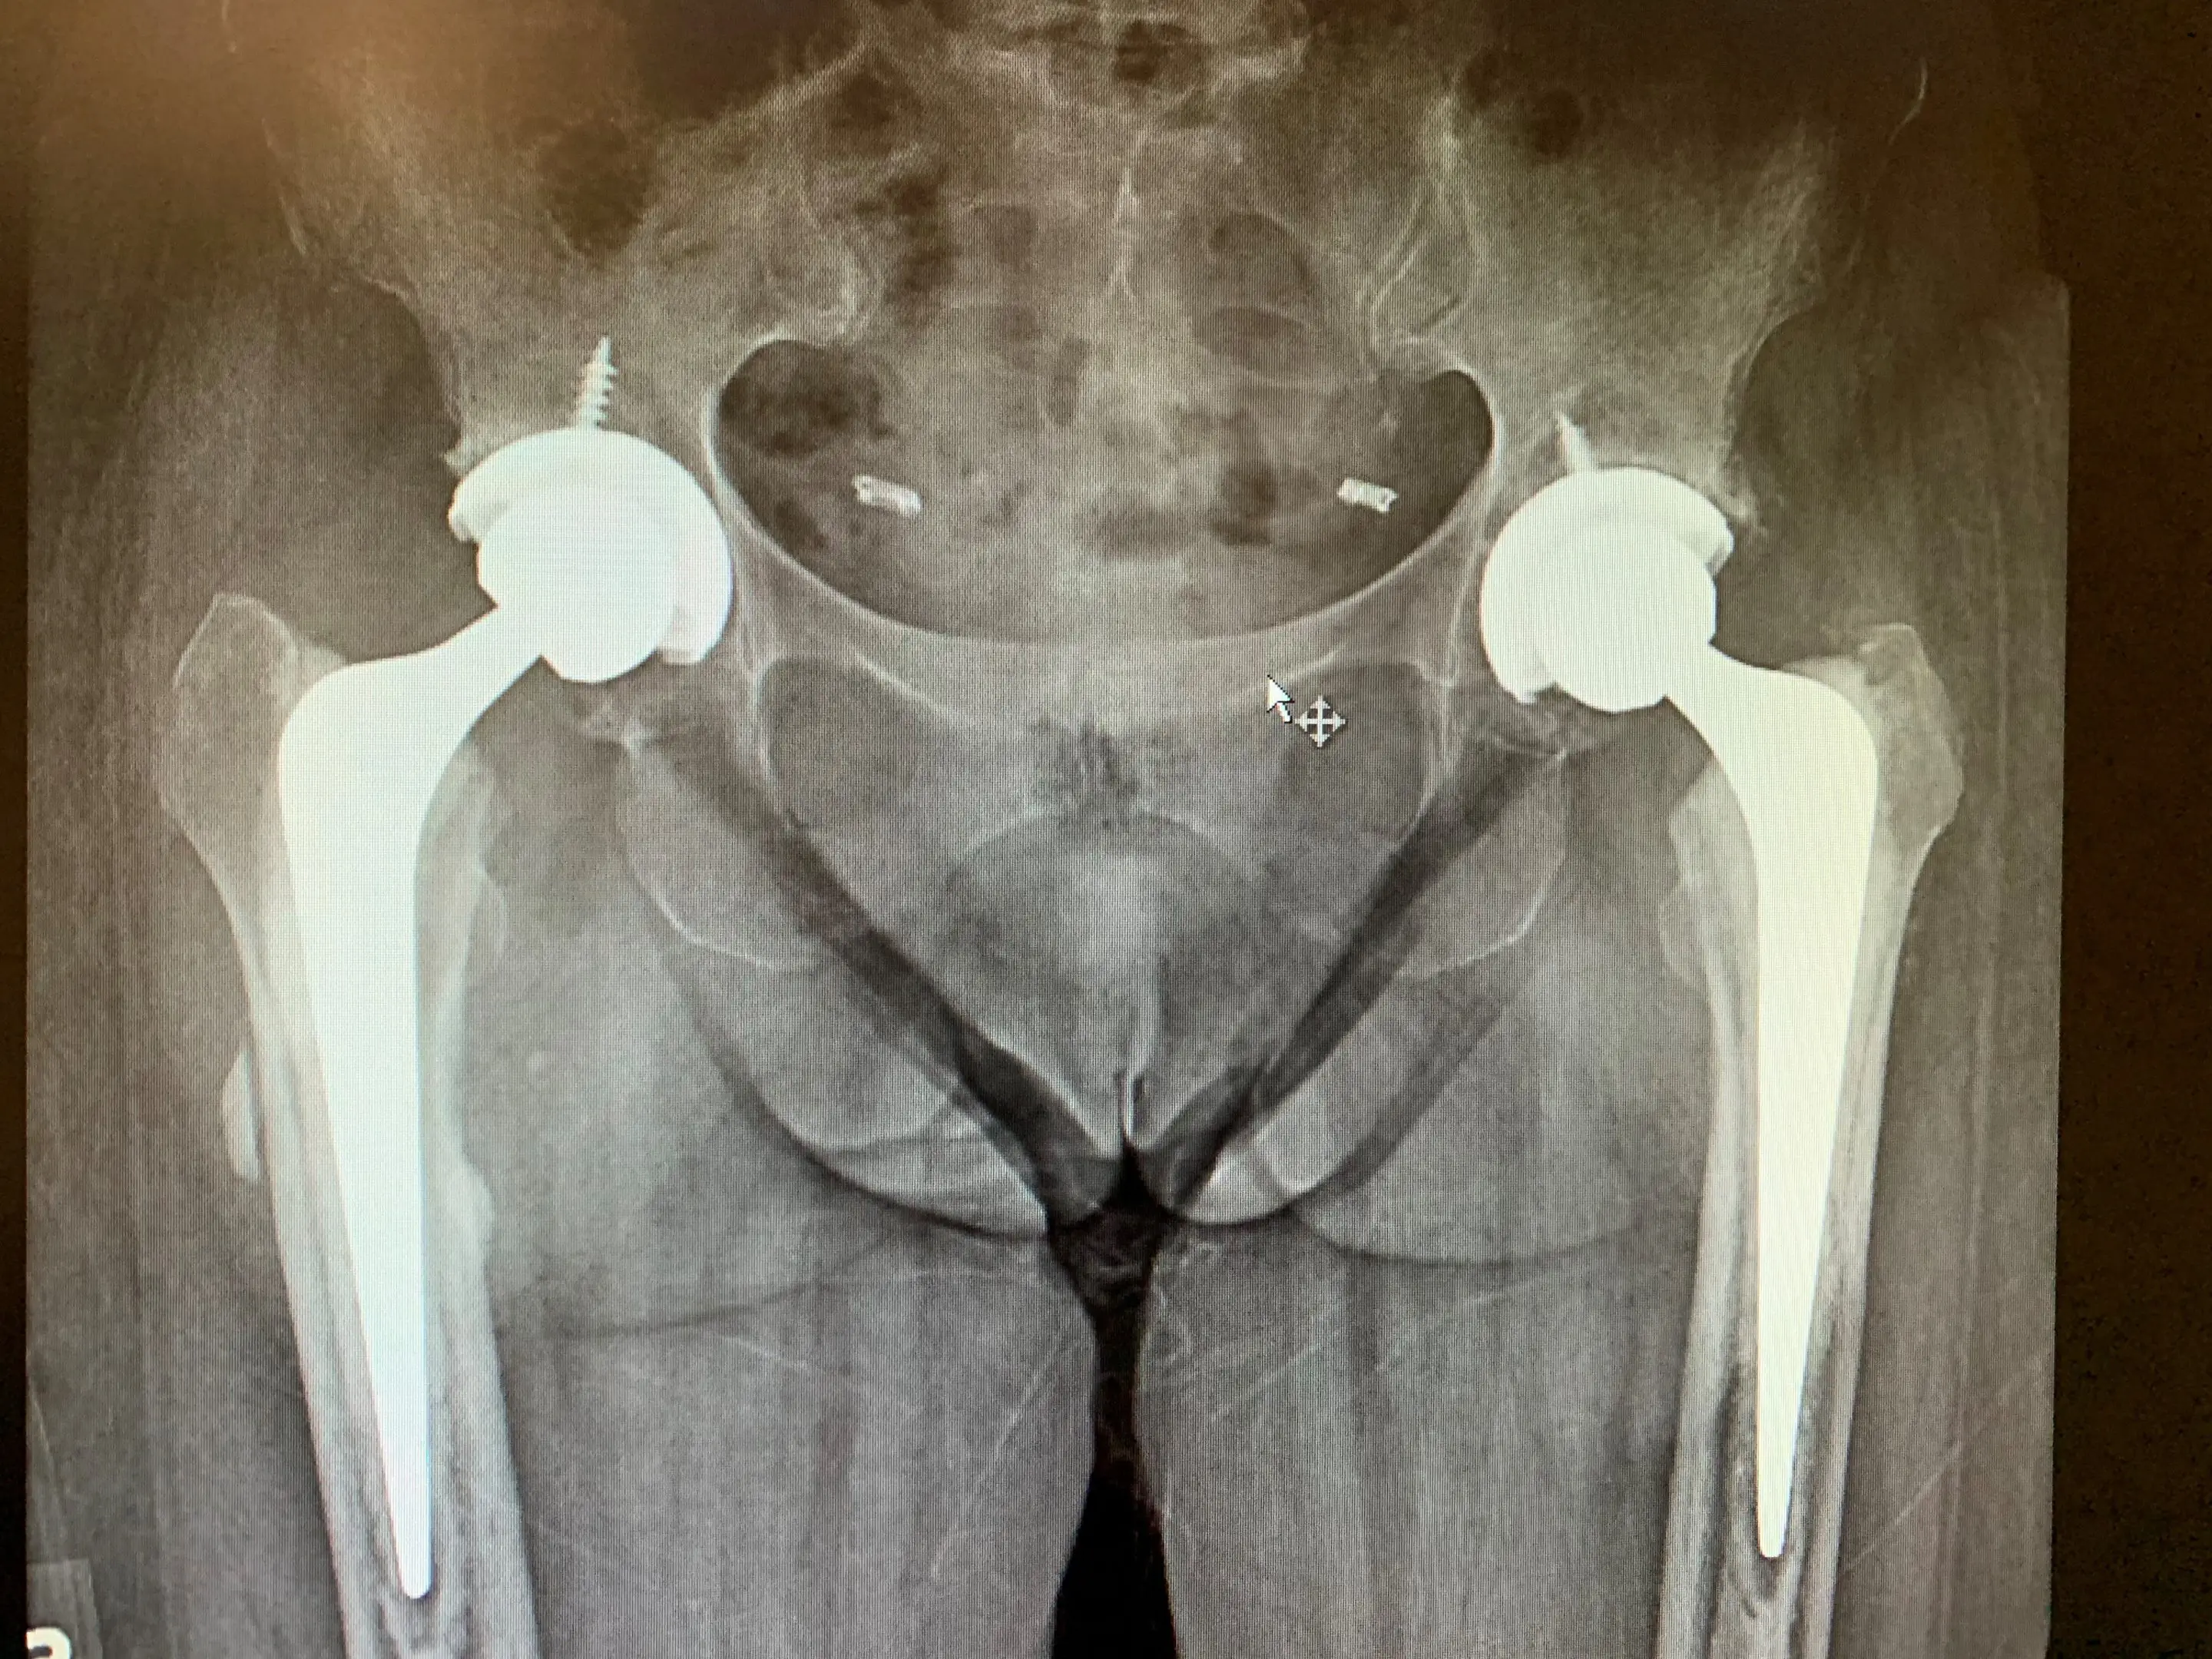

We explained that, should she would be a candidate for simultaneous bilateral anterior Total Hip Arthroplasty given her lack of medical comorbidities and her essentially equal severity of arthritis in each hip. She was agreeable to this, and provided informed consent.

We performed her anterior approach hip replacements on a special table that enable us to manipulate each leg independently. We completed her left hip replacement before starting the right side, but all under the same general anaesthesia.

Post-op